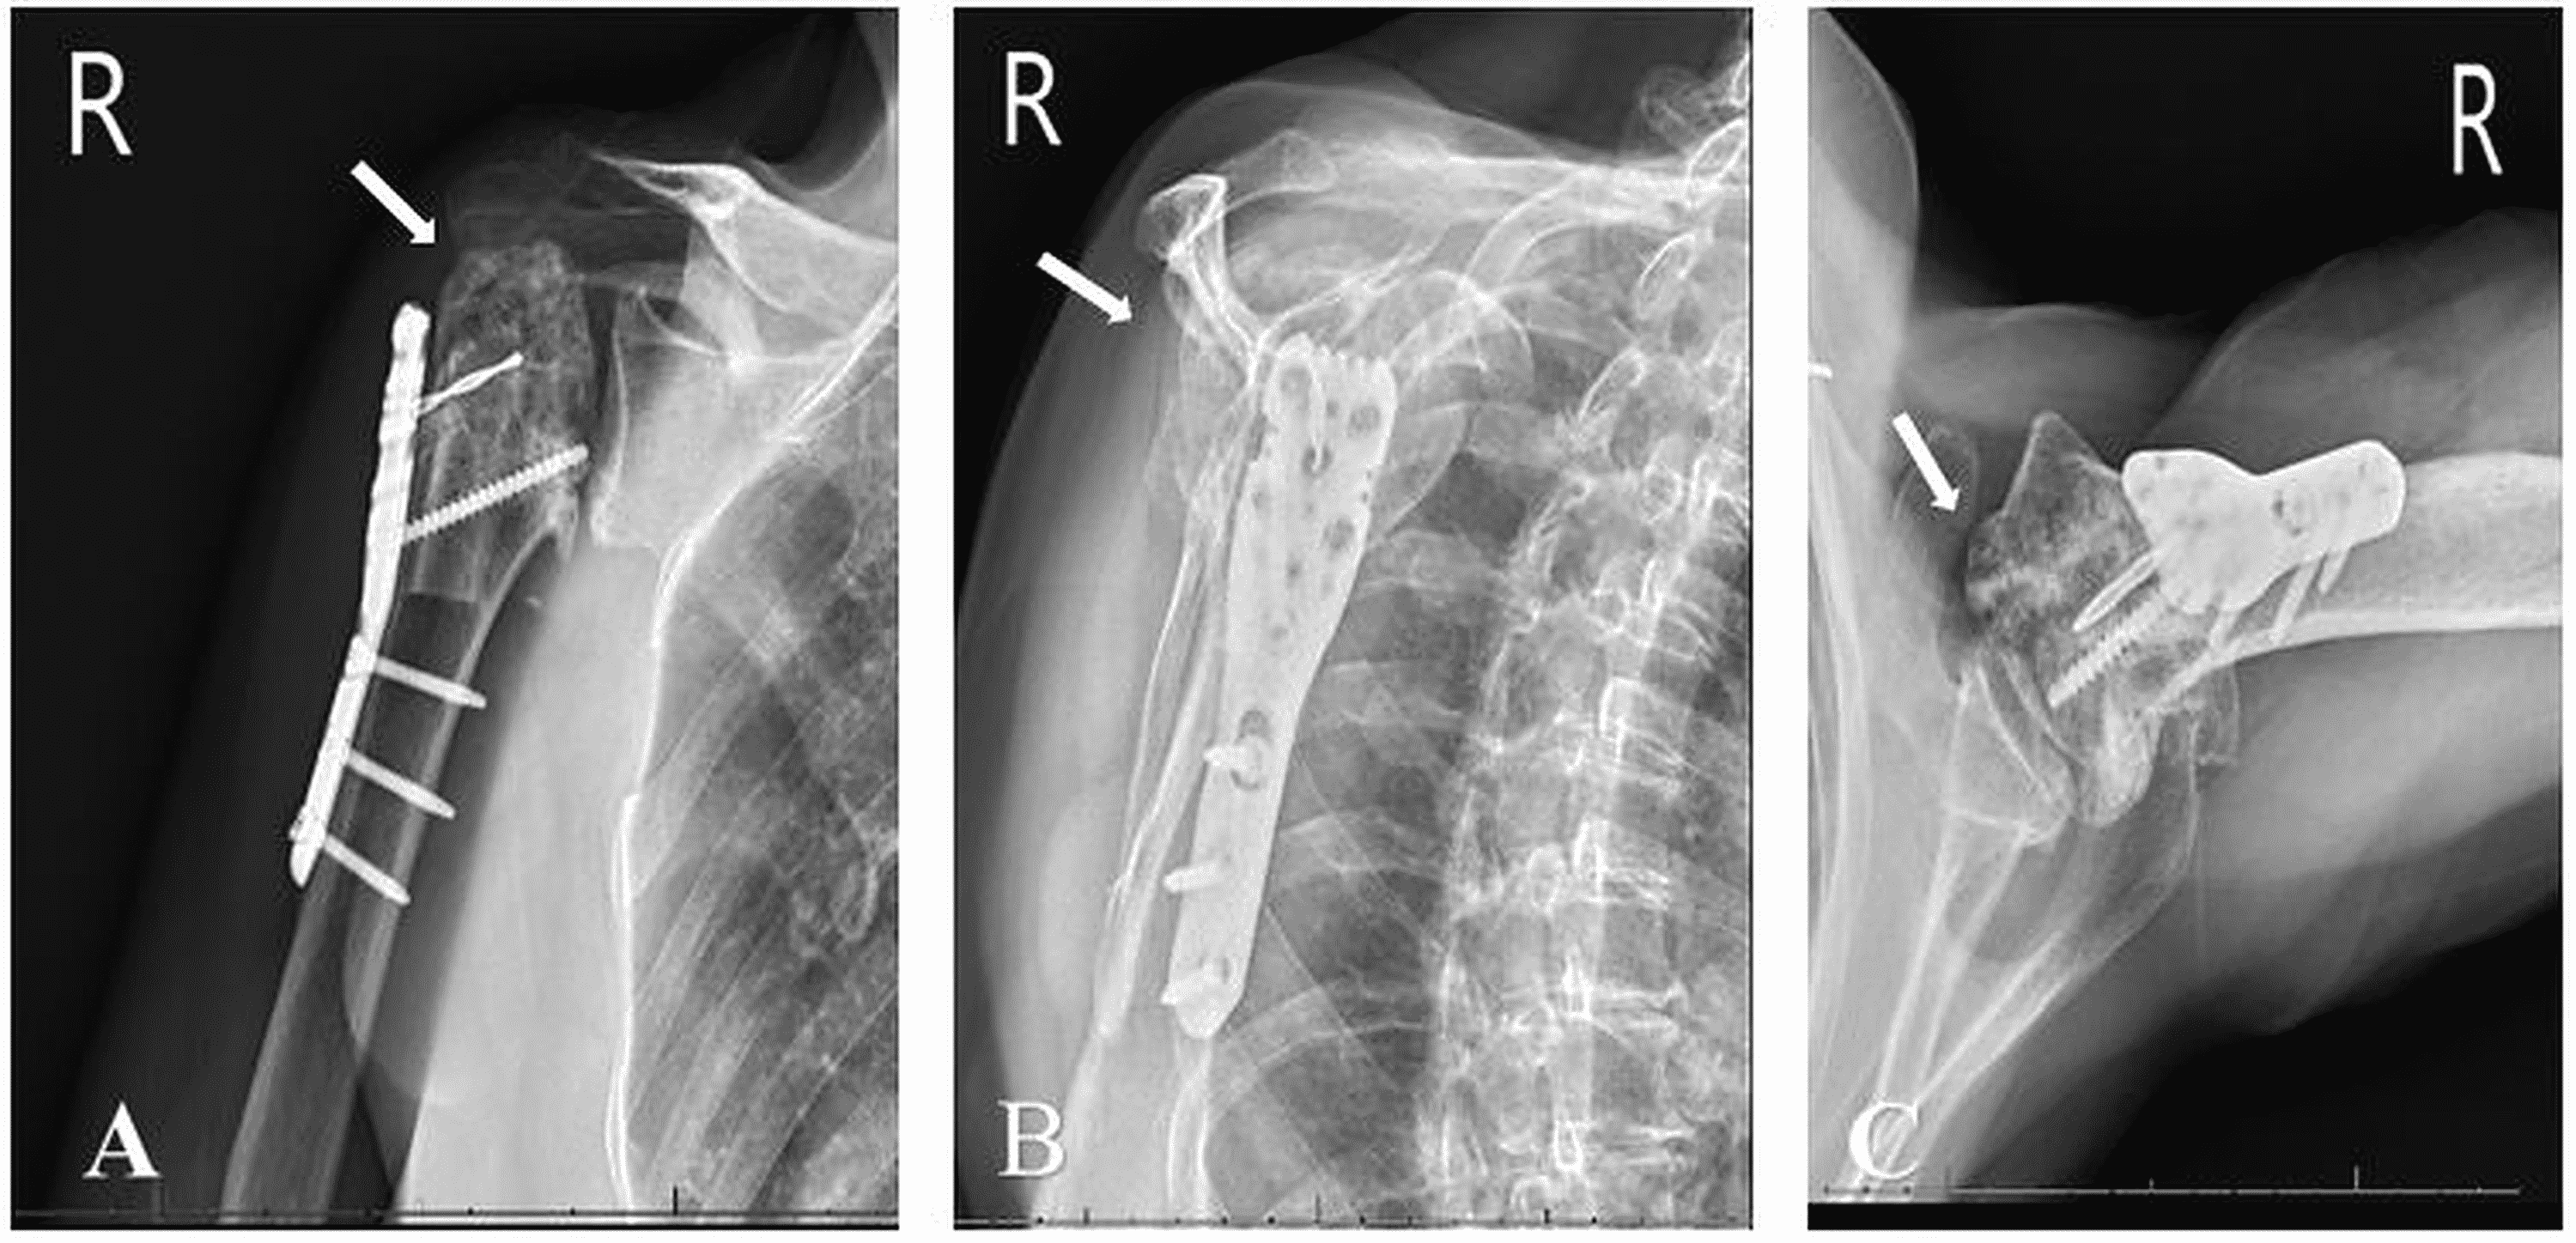

Proximal Humerus Fracture Orif

Proximal Humerus Fracture Orif Range Of Motion After Proximal Humerus Fracture Describe the typical clinical presentation of a patient with a proximal humerus fracture. Due to limited movement following a proximal humerus fracture, you may lose range of motion in your shoulder. This can lead to stiffness of the shoulder joint. Your physical therapist will assess your shoulder motion compared to expected normal motion and the motion of shoulder of your. Range Of Motion After Proximal Humerus Fracture.